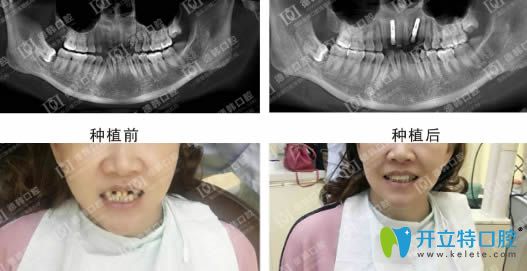

說一千,道一萬,武漢德韓種植牙到底怎么樣,不如效果展示來的實(shí)在:

德韓口腔種植牙效果前后對比圖

武漢德韓口腔憑借先進(jìn)的臨床影像采集技術(shù)、口內(nèi)模型掃描取像及團(tuán)隊醫(yī)師會診等一體化流程,結(jié)合CAD/CAM技術(shù),實(shí)現(xiàn)種植體的精確植入,有效保護(hù)神經(jīng)和血管,保障您的安全與長期使用效果?,F(xiàn)在,武漢德韓口腔為您提供進(jìn)口種植牙服務(wù),僅需3980元,并由種植博士親自診療,歡迎前來咨詢體驗(yàn)。